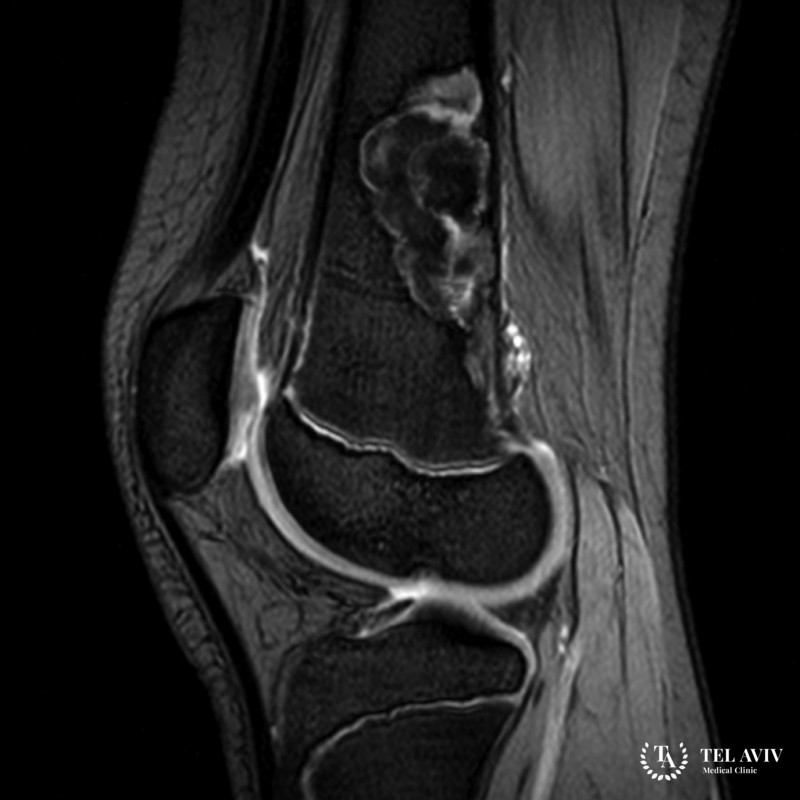

Хондромиксоидная фиброма – это редко встречающаяся доброкачественная опухоль, возникающая в метафизах и метадиафизах длинных трубчатых костей, но может встречаться и в других костях. Основная опасность патологии заключается в том, что опухоль склонна к рецидивам и малигнизации (озлокачествлению).

Диагностика проводится с помощью рентгенографического исследования. Однако зачастую для уточнения диагноза и определения характера неоплазии необходима биопсия.